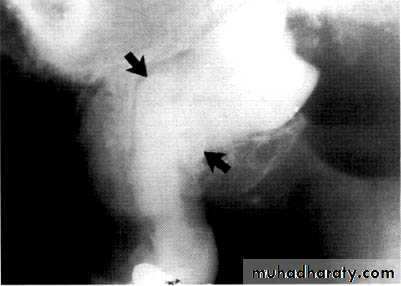

Dilacerated root. The apical portion of the root is bent buccally or lingually into the plane of the central ray. Note the halo in the apical region, produced by the PDL

space (arrow).